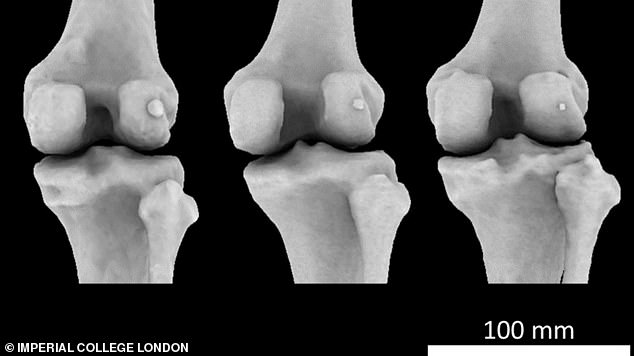

اكتشف علماء من جامعة كلية لندن الإمبراطورية، عظمة إضافية في الركبة، قد تكون السبب وراء التهاب المفاصل، في اكتشاف قد يغير عدد العظام في جسم الإنسان والبالغة 206 عظمات.

وتُعرف العظمة باسم ”الفويلة“، وهي عظمة صغيرة تقع داخل الوتر خلف الركبة يصغر حجمها عن 1 سم، توجد في 10-30 % من البشر، وأُطلق عليها اسم ”الزائدة الدودية للعظام“؛ لأنها غير مهمة، كما أنها توجد عادة لدى القطط والكلاب.